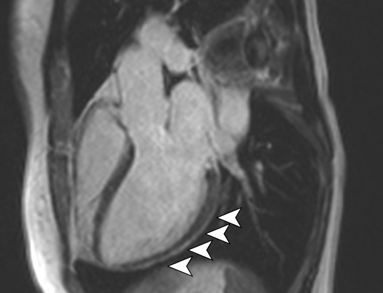

Myocarditis Symptoms Covid : Myocarditis and COVID vaccine - a rare event that may not be linked - News Break / Myocarditis often has no symptoms.. Am j med case rep. The possible pathophysiology and proposed guideline. Symptoms of myocarditis include chest pain, shortness of breath, fatigue, and fluid accumulation in the lungs. Symptoms of myocarditis and pericarditis can vary but often include. Myocarditis, also known as inflammatory cardiomyopathy, is inflammation of the heart muscle.

Indirect myocardial injury, myocardial inflammation or myocarditis? Symptoms can include shortness of breath, chest pain, decreased ability to exercise, and an irregular heartbeat. Treatment for myocarditis depends on the cause. Symptoms of myocarditis and pericarditis can vary but often include. Common symptoms include headache, loss of smell and taste, nasal congestion and runny nose, cough, muscle pain, sore throat, fever, diarrhea, and breathing difficulties. Myocarditis, also known as inflammatory cardiomyopathy, is inflammation of the heart muscle. Symptoms of myocarditis include chest pain, shortness of breath, fatigue, and fluid accumulation in the lungs. In fact, most people recover and never even. Myocarditis care at mayo clinic. If true, this could, in part, explain some of the observed cardiac injury and arrhythmias in. Treatment mainly involves preventing heart failure with medication and diet. Myocarditis often has no symptoms. Am j med case rep.